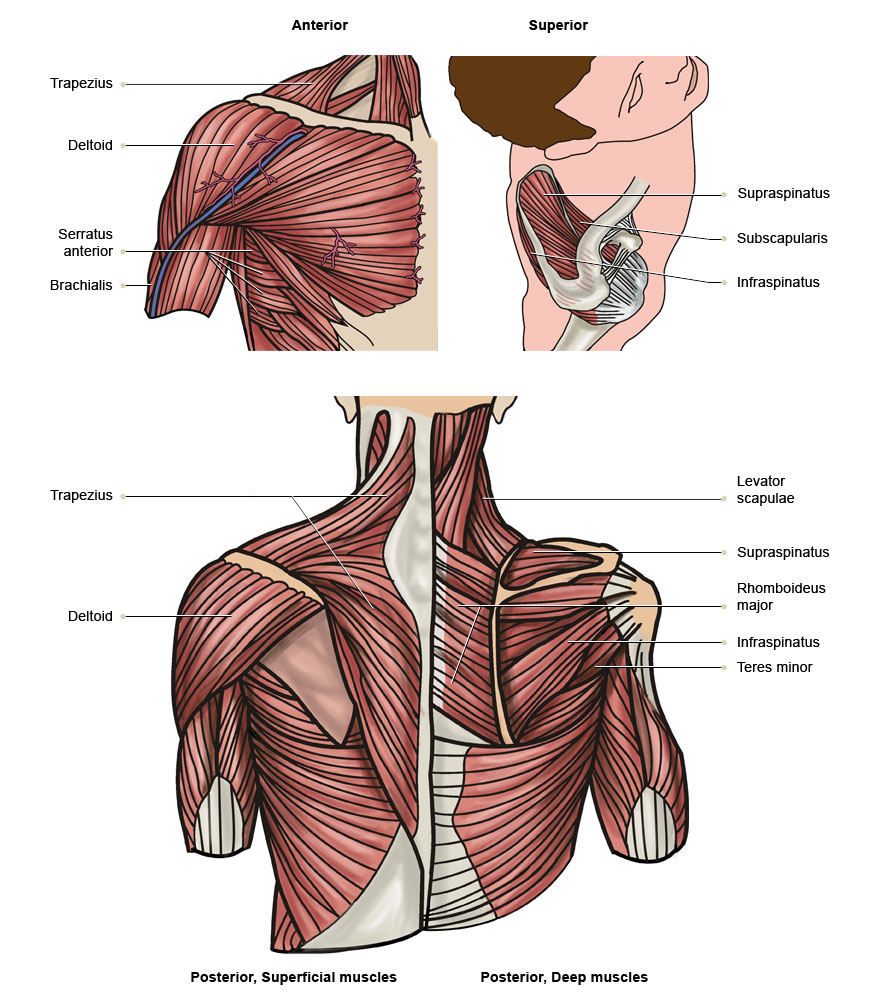

Фотографии поддельтовидной мышцы плечевого сустава